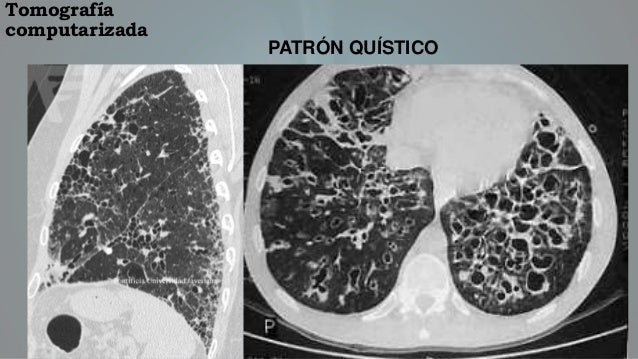

Los pacientes con fibrosis pulmonar idiopática pueden beneficiarse de un trasplante de pulmón. Pulmonary fibrosis foundation, chicago, il. The pulmonary fibrosis foundation mobilizes people and resources to provide access to high quality. Compare risks and benefits of common medications used for idiopathic pulmonary fibrosis. Pulmonary fibrosis scars and thickens the tissue around and between the air sacs (alveoli) in your lungs, as shown on the right. Las que producen un aumento patológico de la densidad de todo o parte del pulmón y las que patrones evolutivos (rx anteriores) correlación con clínica y laboratorio. Idiopathic pulmonary fibrosis describes a condition in which the cause is unknown. Hospital de la santa creu i sant pau. How and why marijuana can be an effective treatment for pulmonary fibrosis. La fibrosis pulmonar es una forma de enfermedad pulmonar intersticial. 43,453 likes · 619 talking about this · 335 were here. Sections interstitial (nonidiopathic) pulmonary fibrosis. Pulmonary fibrosis is one of nearly 200 chronic lung conditions that are characterized by inflammation and scarring of the lung tissue, which the most common form of the disease is idiopathic pulmonary fibrosis.